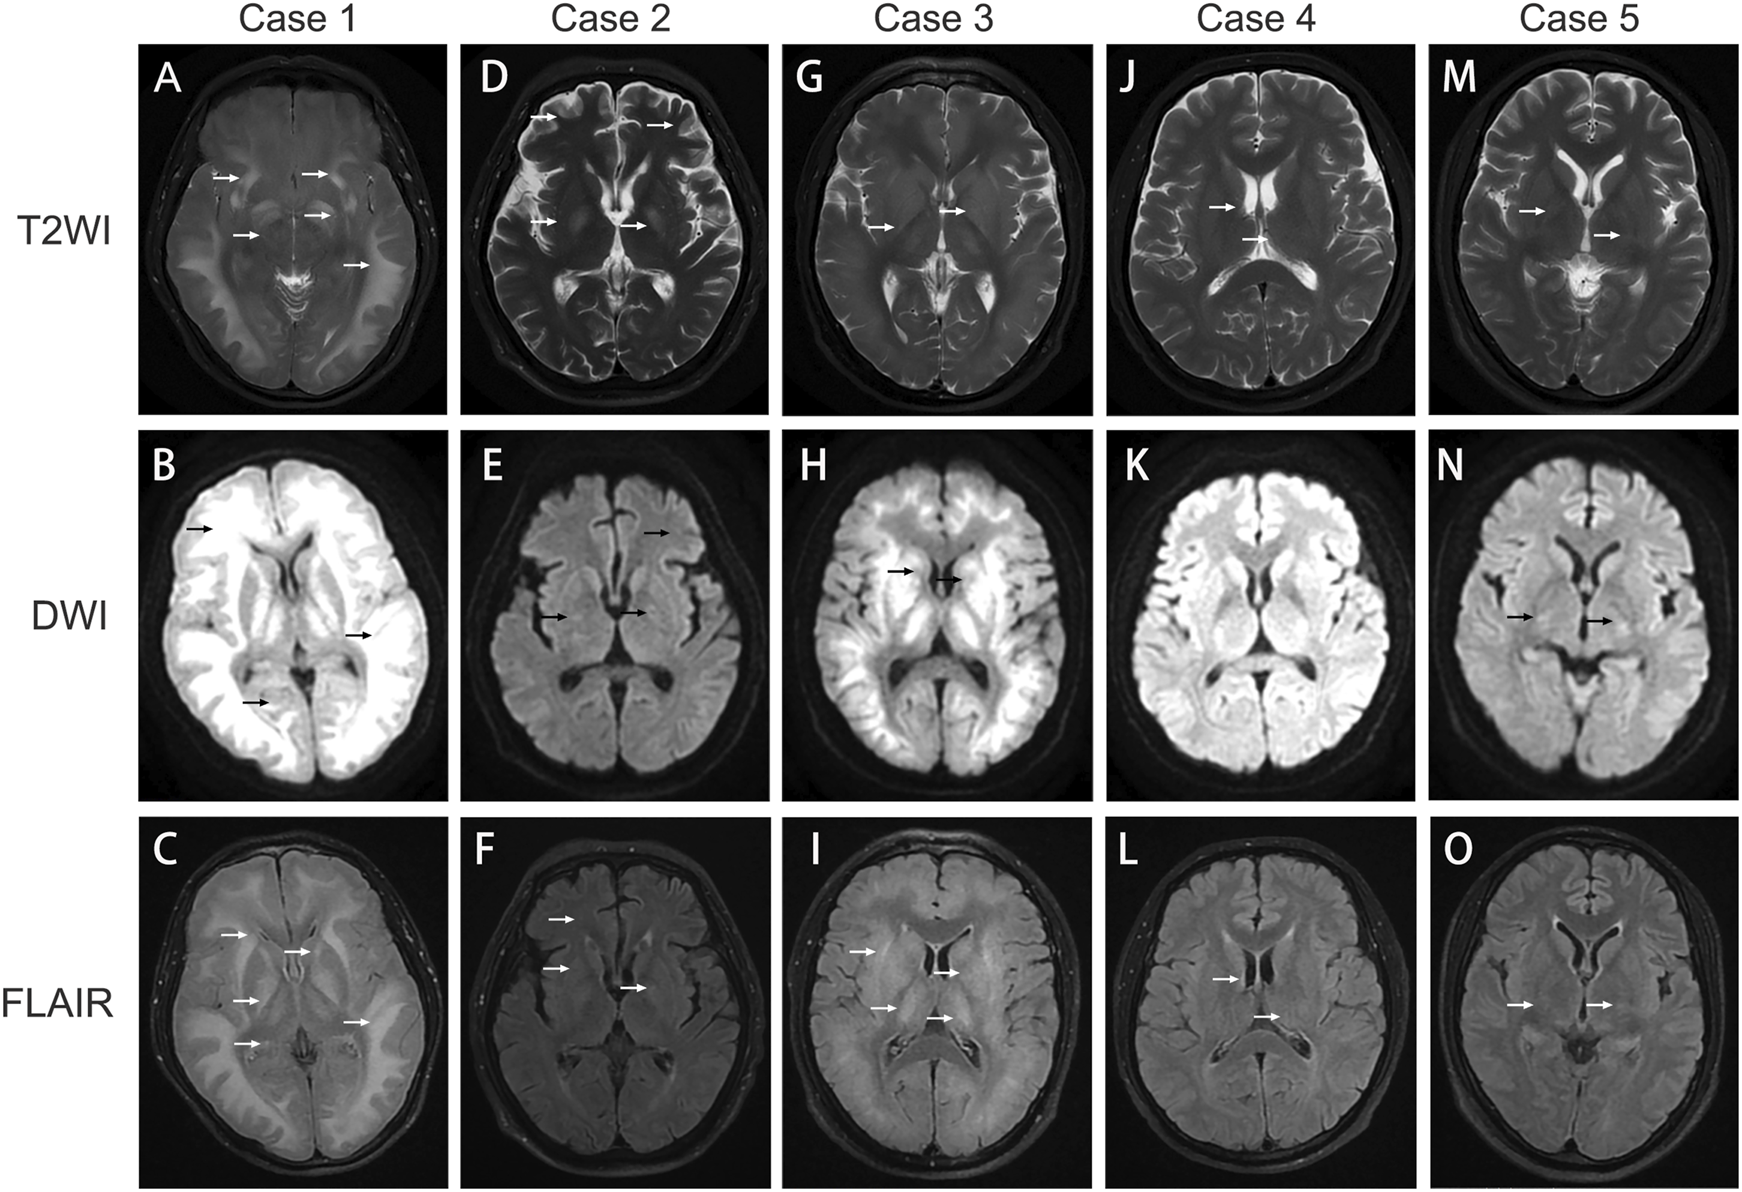

FIGURE 2

Image findings in 1,2‐DCE induced toxic encephalopathy. (A–C) cerebral MRI images of Case 1; (D–F) cerebral MRI images of Case 2; (G–I): cerebral MRI images of Case 3; (J–L): cerebral MRI images of Case 4; (M–O) cerebral MRI images of Case 5. T2WI: T2‐weighted imaging; DWI: diffusion‐weighted imaging; FLAIR: fluid‐attenuated inversion recovery. The arrows indicate cerebral lesions associated with toxic encephalopathy.

A 31-year-old male patient presented with unexplained alterations of consciousness commenced approximately 25 days prior to his clinic visit. Prior to the onset of the illness, the patient had worked as a plumber and been exposed to polyvinyl chloride (PVC) glue for approximately 14 days. During this period, he experienced intermittent recovery of consciousness accompanied by symptoms such as decreased memory, calculation, and comprehension abilities, intermittent headaches, vomiting, and diplopia. Recently, he had recurrently relapsed unconscious and was subsequently transferred to our hospital. Upon admission, the man was in a lethargic state, responsive to verbal stimuli with partial accuracy in answering questions but unable to follow commands. He exhibited decreased memory, calculation, and comprehension abilities. Vital signs remained stable, and laboratory biochemical tests as well as cerebrospinal fluid analysis yielded no significant abnormalities. Cranial magnetic resonance imaging (MRI) showed scattered hyperintensity signals in the bilateral white matter and basal ganglia on T2-weighted imaging (T2WI), diffusion weighted imaging (DWI), and fluid-attenuated inversion recovery (FLAIR) (Figures 2A–C), which indicative of toxic encephalopathy. Chest computed tomography (CT) indicated the presence of lung infection. Investigation of his occupational history revealed exposure to adhesive containing 1,2-DCE prior to the onset of illness. The man was diagnosed with 1,2-DCE induced toxic encephalopathy and received treatment with mannitol (125 mL, three times daily) for dehydration, dexamethasone (5 mg daily) to prevent cerebral edema. Levetiracetam (0.5 g, twice daily), phenobarbital, and intravenous valproate were given to alleviate seizures and convulsions. After 3 days of treatment, the patient fell into a coma, and suffered a sudden spontaneous breathing cease. Advanced life support was performed immediately, and the patient was transferred to the intensive care unit after returning spontaneous circulation. A cranial CT scan demonstrated extensive cerebral tissue swelling, with hypodensity areas in the white matter regions of the bilateral cerebral hemispheres and dentate nuclei. Treatment included mild hypothermia for neuroprotection, antiepileptic therapy with levetiracetam (0.5 g, twice daily), intravenous phenobarbital, and mannitol (125 mL, three times daily) to alleviate intracranial pressure, and cefoperazone-sulbactam (3 g, 8 h daily) for lung infection. Ten days later, the clinical condition of the man worsened, manifesting as anemia, thrombocytopenia, and coagulation abnormalities. The procalcitonin level was 12.73 ng/mL, neutrophil count was 95.9%, hemoglobin level was 61 g/L, platelet count was 9 × 10^9/L. Platelets, red blood cell suspensions, and fresh frozen plasma transfusions were administered, and meropenem (1 g, three times a day) was substituted for cefoperazone-sulbactam. During subsequent treatment, the man developed refractory acidosis and respiratory failure, ultimately resulting in death.

A 56-year-old male patient worked as a plumber with a history of exposure to PVC glue in a confined workspace several months ago. Approximately 27 days before admission, the patient experienced symptoms of dizziness, fatigue, vomiting, and diarrhea. Notably, two colleagues also manifested similar symptoms but recovered after changing their job assignments. A few days before hospital admission, his condition deteriorated, manifesting as disturbed consciousness with recurrent limb convulsions and incontinence. The patient visited another hospital and a brain CT scan was performed, while yielding no remarkable findings. After unsuccessful treatment, he was transferred to our hospital. Upon admission, the patient was comatose with intermittent limb convulsions, blood biochemistry tests indicated the hemoglobin level of 77 g/L, while other biochemical tests were unremarkable. Head CT scans indicated no brain parenchyma swelling, while chest CT scans revealed bilateral minimal pleural effusion and partial atelectasis with consolidation in the lower lobes of both lungs. Given the occupational exposure and symptoms of the patient, a suspicion of chemical poisoning from PVC glue arose. Detection of 1,2-DCE in the PVC glue led to a diagnosis of acute 1,2-DCE poisoning. The patient received sodium valproate (0.2 g, twice daily), and levetiracetam (0.5 g, twice daily) for seizure control, mannitol (125 mL, three times daily) to reduce intracranial pressure and alleviate cerebral edema. Hyperbaric oxygen therapy (2.0 atm of pressure, 2 hours daily) was administered to improve cerebral oxygen metabolism and promote neural function recovery. Cefoperazone-sulbactam (3 g, three times daily) was given for lung infection, and nutrition support was provided. After 10 days of hospitalization, the frequency of limb convulsions significantly diminished and completely disappeared after 13 days, but the consciousness disorders did not improve. A cerebral MRI was performed to reassess the cerebral lesions, T2WI, FLAIR, and DWI imaging disclosed multiple nodular areas of increased signal intensity in the subcortical regions of the bilateral frontoparietal lobes and periventricular areas (Figures 2D–F). Despite undergoing a 33-day treatment regimen, no significant improvement was observed in the consciousness disorders, and the man was discharged from hospital for continued rehabilitation. A 3-month follow-up showed no enhancement in his consciousness disorder.

A 37-year-old male patient presented with symptoms of dizziness, headache, and diminished responsiveness over 10 days before admission. He reported a history of chronic exposure to PVC adhesive in his occupational environment. Head MRI performed at a local hospital revealed symmetric abnormal high-density signals in the subcortical white matter regions of the bilateral cerebral hemispheres, brainstem, cerebellar dentate nuclei, and basal ganglia, suggesting a likelihood of toxic encephalopathy. Consequently, the patient was transferred to our hospital for further management. Upon admission, the patient demonstrated significant cognitive decline and reduced responsiveness, while other physical examinations were unremarkable. MRI findings included patchy abnormal signal intensity in the bilateral subcortical regions, basal ganglia, bilateral thalamus, and dentate nuclei of the cerebellum. The FLAIR sequence exhibited increased signal, and DWI displayed restricted diffusion, further implicating potential toxicity or metabolic encephalopathy (Figures 2G–I). The forensic identification center detected the presence of 1,2-DCE within the adhesive that the patient had been in contact with. Based on the findings, a diagnosis of acute 1,2-DCE induced toxic encephalopathy was confirmed. The man was administered mannitol (125 mL, three times daily) to alleviate intracranial pressure, along with methylcobalamin (0.5 mg intravenous daily), and citicoline sodium (0.5 g intravenous daily). Additionally, hyperbaric oxygen therapy (2.0 atm of pressure, 2 hours daily) was provided. Following more than 2 weeks of hospitalization, the symptoms disappeared. A follow-up assessment was conducted 3 months post-discharge, revealing improvement in symptoms and resumption of normal daily activities.

A 50-year-old man who had been working at a construction site for several months had been exposed to PVC adhesive for pipe bonding over the past 2 weeks. Over the preceding 18 days, he developed symptoms of delayed response, dizziness, and gait instability. These symptoms intensified the day before hospital admission, accompanied by involuntary tremors in all extremities. Upon admission, physical examination disclosed decreased reactivity and mild cognitive impairment, particularly in calculation and orientation skills. Initial laboratory tests did not reveal any abnormalities. A cranial MRI demonstrated striped and patchy abnormal signals adjacent to the lateral ventricles and centrum semiovale in T2WI and FLAIR, while no significant abnormal signals were detected on DWI (Figures 2J–L). The electromyogram of the limbs indicated a slight decrease in the sensory wave amplitude of the left ulnar nerve compared to the right, with normal conduction velocity. The F-waves of bilateral ulnar, median, and tibial nerves were normal, and the H-reflexes of bilateral tibial nerves were within normal ranges. The man received treatment with mannitol (125 mL, three times daily), mecobalamin, and hyperbaric oxygen therapy (2.0 atm of pressure, 2 hours daily). Following approximately 2 weeks of treatment, his reactivity enhanced, dizziness diminished, and extremity tremors resolved. At a 3-month follow-up appointment after discharge, the cognitive function, calculation abilities, and orientation had notably improved, without any adverse effect on his daily activities.

A 32-year-old man was admitted to our hospital with a 1-day history of dizziness and vomiting, followed by a prolonged seizure episode lasting over 10 h, accompanied by altered mental status. The patient had been exposed to PVC adhesive in a poorly ventilated, approximately 1-square-meter with a height of 3-m workplace while brushing pipes. The man did not wear protective gloves during work and only wore a regular protective face mask. He worked continuously for 6 days before hospital admission, approximately 5–7 h each day. On the preceding day, the patient experienced dizziness, nausea, vomiting, and developed to coma. Upon presentation, he exhibited tachypnea and seizures involving all four limbs. Laboratory tests revealed the interleukin-6 was 69.45 pg/mL, and procalcitonin was 0.75 ng/mL, and the lactate level was 5.67 mmol/L. Elevation in white blood cell count, alanine aminotransferase and aspartate aminotransferase was revealed. Cranial MRI demonstrated abnormal signal intensity in the bilateral basal ganglia (Figures 2M–O), while no abnormality was detected on head CT. Chest CT imaging demonstrated bilateral lung infections with consolidation in the lower lobes and minimal pleural effusion. The patient received invasive ventilation, citicoline sodium (0.5 g intravenous daily), along with hyperbaric oxygen therapy (2.0 atm of pressure) twice-daily. Sodium valproate and ceftriaxone (2 g daily) were administered intravenously for seizure management and pulmonary infection. After 7 days of treatment, the patient regained consciousness and was successfully weaned off ventilator support, although intermittent seizures and restlessness persisted. After 32 days of hospitalization, the motor function of the man exhibited improvement, however, he remained non-ambulatory and wheelchair-dependent. Consequently, the patient was discharged for rehabilitation therapy. During the 3-month follow-up, the man demonstrated the ability to ambulate with assistance.

1,2-DCE poisoning often has an insidious onset and suddenly deteriorates. Prolonged cerebral edema is a significant clinical feature of 1,2-DCE poisoning (Dang et al., 2019). Head CT scans frequently fail to detect lesions in the early stages, whereas cranial MRI plays a crucial role in diagnosing 1,2-DCE-induced toxic encephalopathy. Head MRI reveals symmetric, diffuse abnormal signal intensity in the bilateral subcortical white matter and basal ganglia area, particularly affecting the cerebellar dentate nucleus, manifesting as high-intensity signals on T2WI and DWI (Zhan et al., 2011; Liu et al., 2019). Other studies have indicated that brain lesions can be observed in regions such as the centrum semiovale, external and internal capsule, thalamus, and even the brainstem and cerebellar hemisphere during the acute phase. In this phase, brain edema primarily arises from cytotoxic mechanisms, while in the subacute phase, the edema mainly attributed to vasogenic factors (Liu et al., 2010; Ridgway et al., 2003). DWI has the capability to detect brain alterations at an earlier stage compared to conventional T2WI (Chen et al., 2015). Notably, a thorough investigation of the occupational exposure history is crucial to prevent misdiagnosis. Intracranial infections or metabolic disturbances can also lead to coma and seizures. Laboratory examinations including cerebrospinal fluid analysis and blood gas analysis, as well as comprehensive physical examinations were necessary for differentiating these conditions.